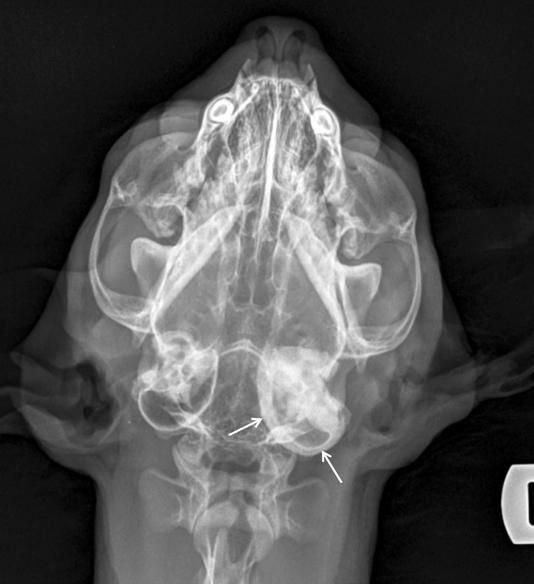

1. Radiografías de la cabeza de un gato maine coon de un año de edad. (A) Proyección lateral. (B) Proyección dorsoventral. (C) Rostro 10º ventrodorsocaudal oblicua.

Se presentó en consulta un gato macho castrado de raza maine coon, de un año de edad y 5,8 kg de peso, remitido con historia de otitis externa desde hacía un mes.

En la exploración otológica se visualizó una masa en el conducto auditivo externo izquierdo, apreciable desde la abertura del pabellón auricular. La masa era sólida, poco móvil y obstruía totalmente el canal auditivo. El resto del examen físico y pruebas de enfermedades víricas fueron normales. En el análisis sanguíneo se evidenció neutrofilia con desviación a la izquierda y trombocitosis.